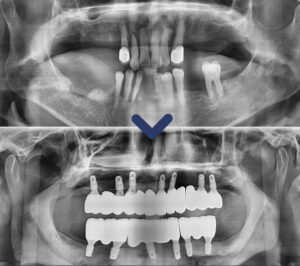

술 후 사진을 보면 상악동이 아래쪽에

위치하고 계신 것을 볼 수 있는데요,

상악동은 사람마다 위치와 크기가

모두 다르기 때문에 필요한 경우에만 시행됩니다.

환자분의 경우 왼쪽 잇몸뼈의 두께가 얇고

상악동이 아래쪽에 위치하고 있어

픽스쳐가 식립 될 공간이 부족하여

상악동 거상술을 시행하였습니다.

상악동거상술은 상악동에 손상이 가지 않도록

막을 들어 올려 빈공간에 뼈를 이식하여

픽스쳐의 식립 공간을 확보해주는 것인데요.

상악동에 손상이 가게 되면 감염이 될 수

있으므로 임상경험이 많으며 숙련된

의료진에게 받는 것이 중요합니다.